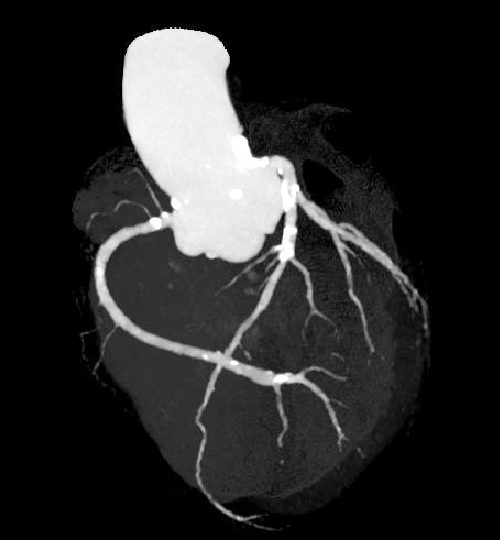

320列CT装置(Aquilion ONE)

最新型320列CT装置で、従来型の64列CT装置に比べて、より精密な検査を短時間で受けることができます。

- 心臓CT撮影が、より簡単に、より低被ばくに行えるようになります。 検出器の列数が一般的に使用されている64列CTの5倍、320列のCTです。 心臓は1心拍分だけの短時間で撮影できるので、検査はすぐに終了します。 1心拍分のスキャンで心臓全体を撮影できるので、従来装置では難しかった不整脈の場合の撮影でも、殆どの場合は問題なくスキャンできます。 最新機種なので、心臓の拍動によるブレをAI(人工知能)技術で修正する機能も搭載しています。また、造影剤もより少ない量で撮影できるので、心臓CT検査のハードルが従来の装置よりもかなり低くなり、どなたでも気楽に検査を受けていただけます。